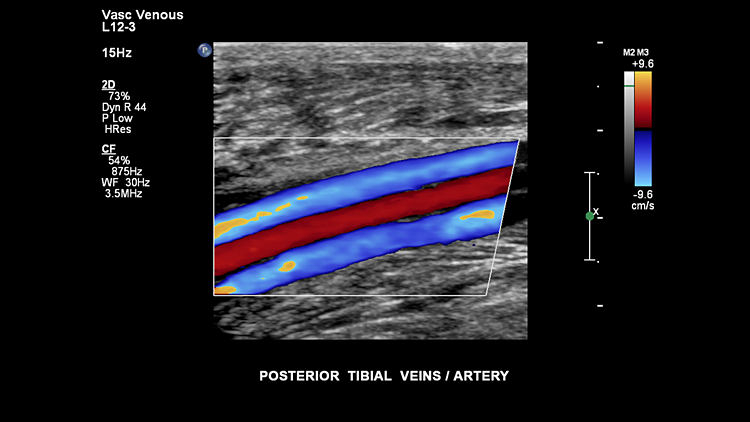

Задние большеберцовые вены, L12-3